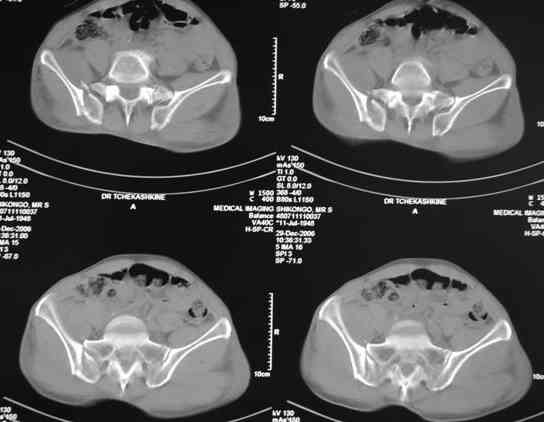

Я помню технику транссакральной фиксации тазового кольца длинными 5 мм Шанцами - повреждения типа В, в этом же случае задний отдел тоже вовлечен

т.е комбинированная нестабильность, поэтому вопрос - достаточно ли только двух Шанцев для стабилизации таза? Что вы думаете об anterior Right SI joint plating + tension band plating from the back.?

По-поводу фиксации таза спонгиозными винтами. Данный способ все-таки показан для фиксации повреждения крестцово-подвздошного сочленения или переломов крестца. Мне кажется, что в данной случае ситуация иная - имеется перелом "основания" крыла подвздошной кости (в который вовлечена и поверхность, составляющая крестцово-подвздошное сочленение). Не уверен, что фиксация данного повреждения (и заднего полукольца) винтами будет стабильной, так как именно на уровне 1-2 крестцовых позвонков (где обычно вводят винты) линия перелома уходит в латеральном направлении от крестцово-подвздошного сочленения.

Я просмотрел томограммы и у меня создалось впечатление, что винтам есть за что *зацепиться*. В сочетании с 5 мм Шанц винтами, проведенными через нижне-переднюю ость спереди назад через КП сочленения -стабильность тазового кольца должна восстановиться. - Это , конечно, при условии , что закрытая рнепозиция будет успешной.

Травма произошла 22 или 23 декабря, ко мне больной попал 26 декабря, 3 января -остеосинтез перелома бедра и внутр.лодыжки.

после КТ отказался от этой идеи - двусторонний перелом крестца в зоне 1 - алярная часть, при попытке низведения правого гемипелвиса теоретически есть вероятность смещения

фрагмента крестца слева.